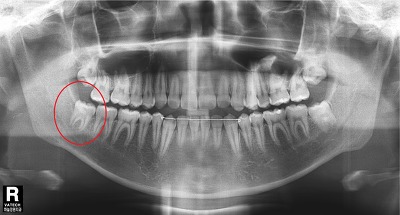

X-ray에서 붉은원 안의 사랑니가 문제입니다.

보기에는 다른 치아와 마찬가지로 멀쩡해 보입니다.